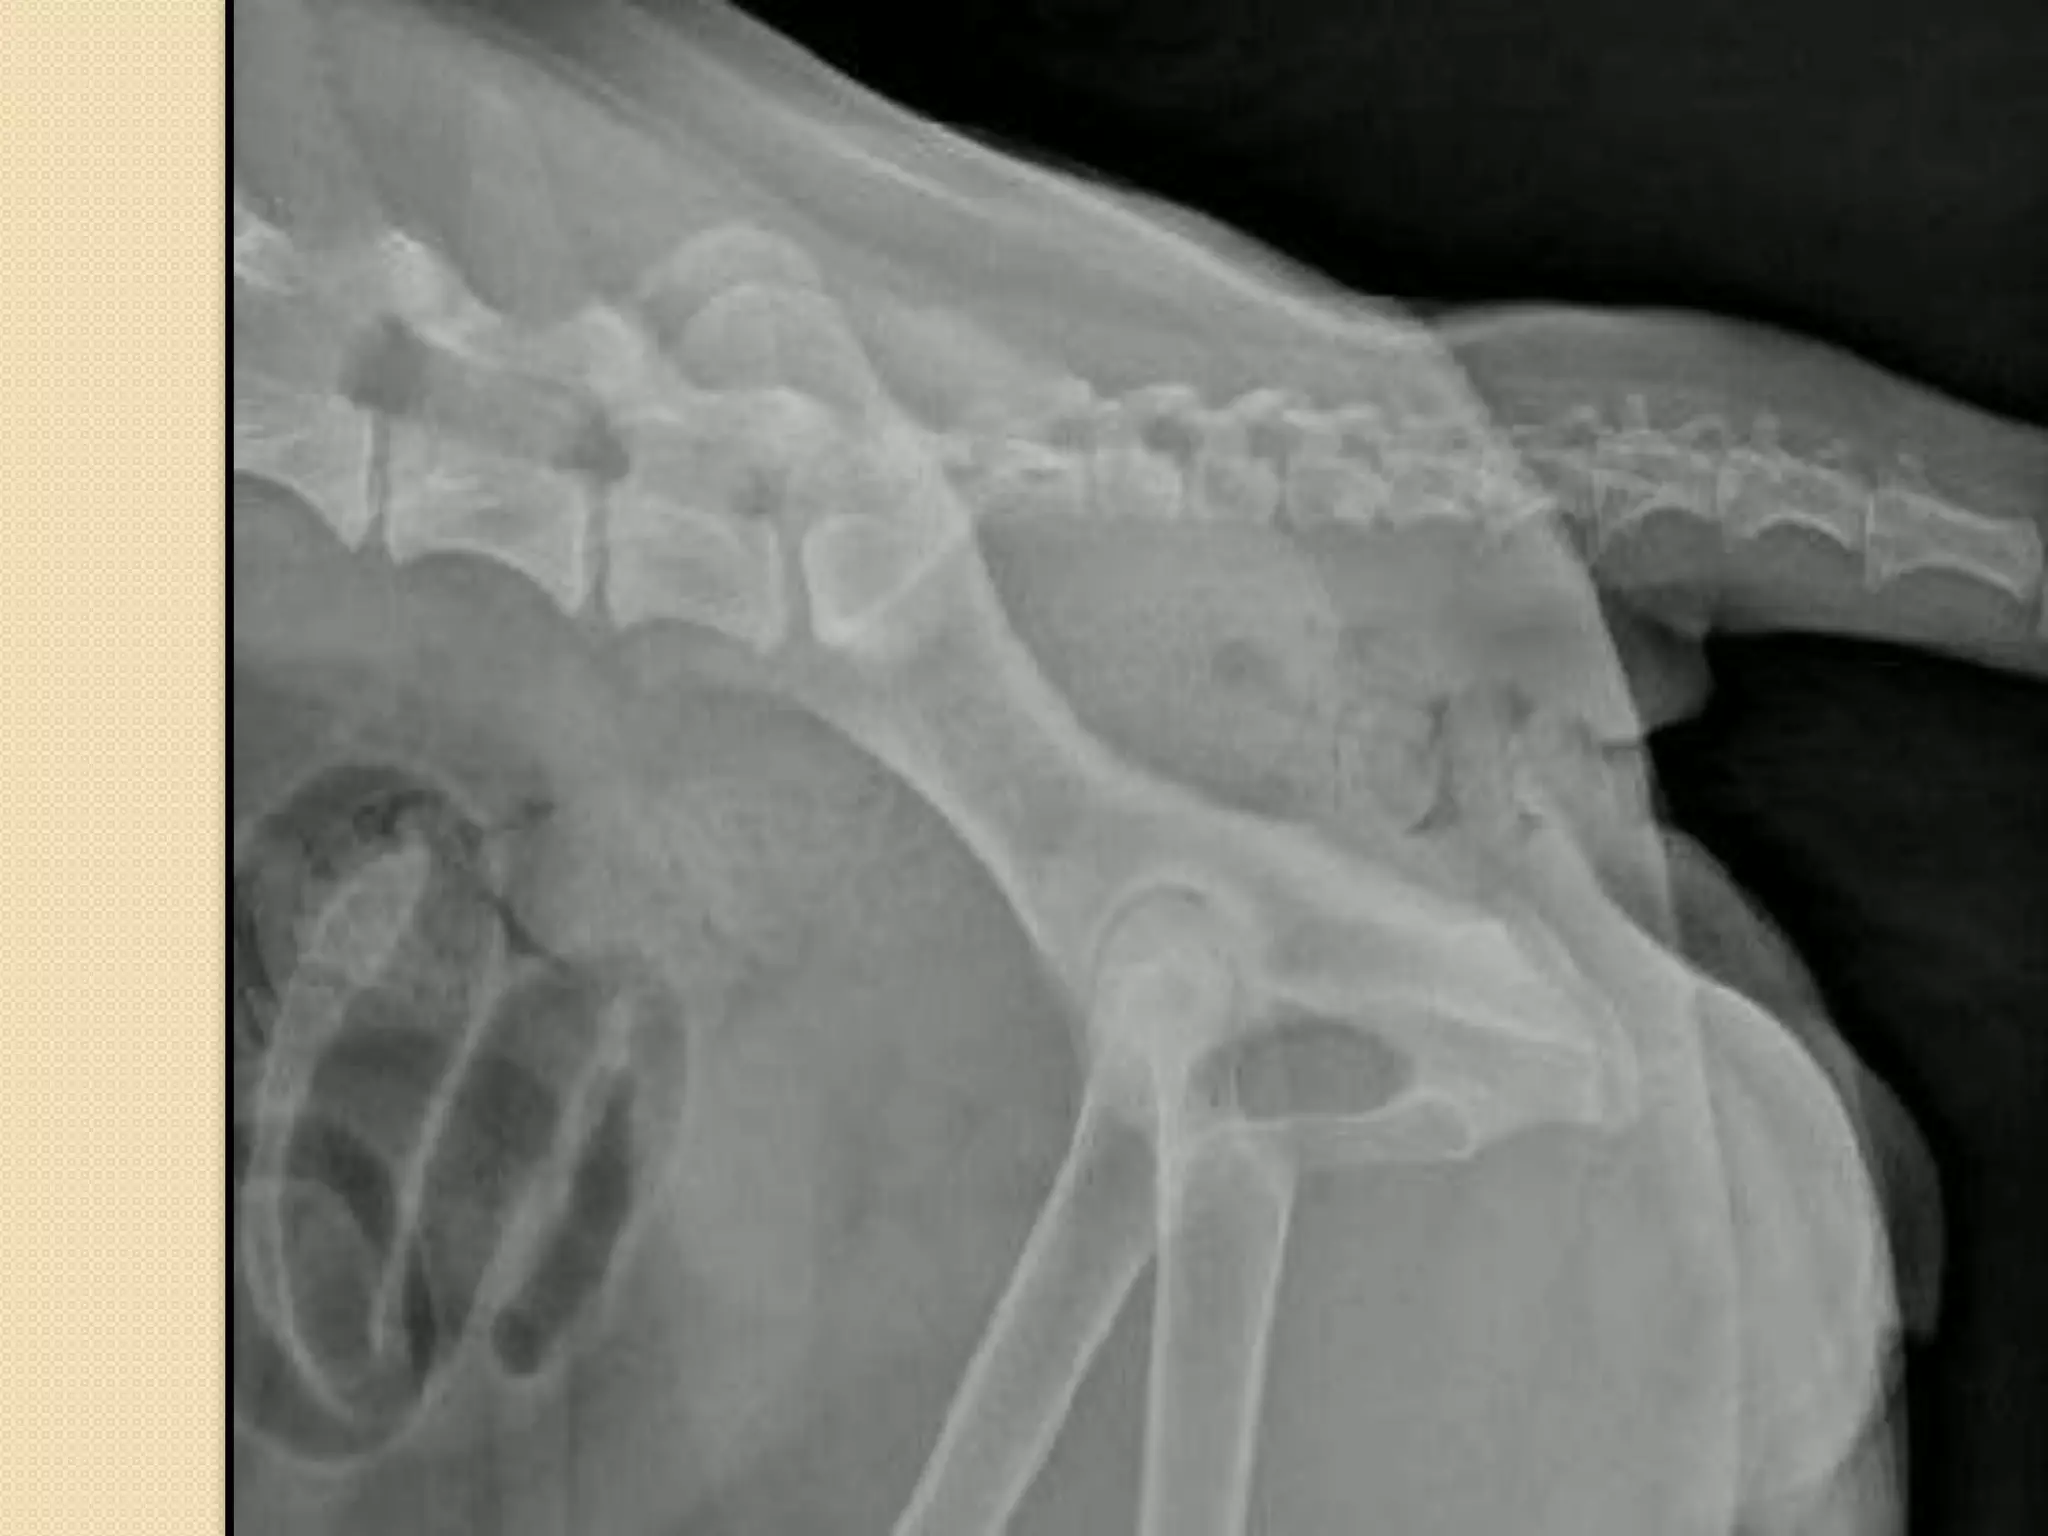

Thoracic vertebrae:

-It is characterised by long spinous process

-The last 3 vertebrae have accessory

processes

-It has articular surface for the rib

articulation

A.Vertebral canal; B.Transverse process;

C. Dorsal spinous process;

D.Vertebral

arch; E. Body;

F. Cranial articular process; H. Cranial costal

fovea.

Ribs:

Each rib is a curved rod, which at its dorsal end is movably

articulated to the vertebra, and at its ventral end is either

connected with the sternum, or ends freely. In the dog there are

thirteen pairs of ribs, nine pairs of which are directly connected

with the sternum, while the remaining four end freely and are

known as floating ribs. Each rib is obviously divided into two

parts, a dorsal or vertebral part, and a ventral or sternal

part. The vertebral portion, which forms about two-thirds of

the whole rib, is a flattened, regularly curved rod, completely

ossified. Its dorsal end is rounded, forming the head or

capitulum, which articulates with a concave surface furnished

partly by the corresponding vertebra and partly by the vertebra

next in front. The last three or four however articulate with one

vertebra only

J. Head;

K.Tuberculum.

Articulation between ribs and thoracic

vertebrae